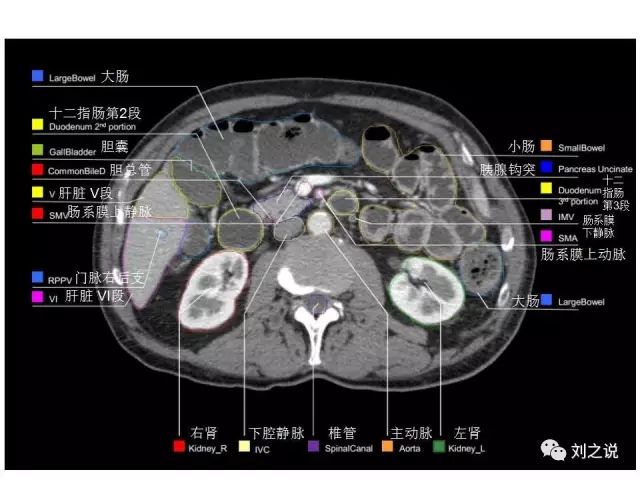

【解剖】高清实用 腹部CT断层

参考RTOG共识和3D-body解剖。